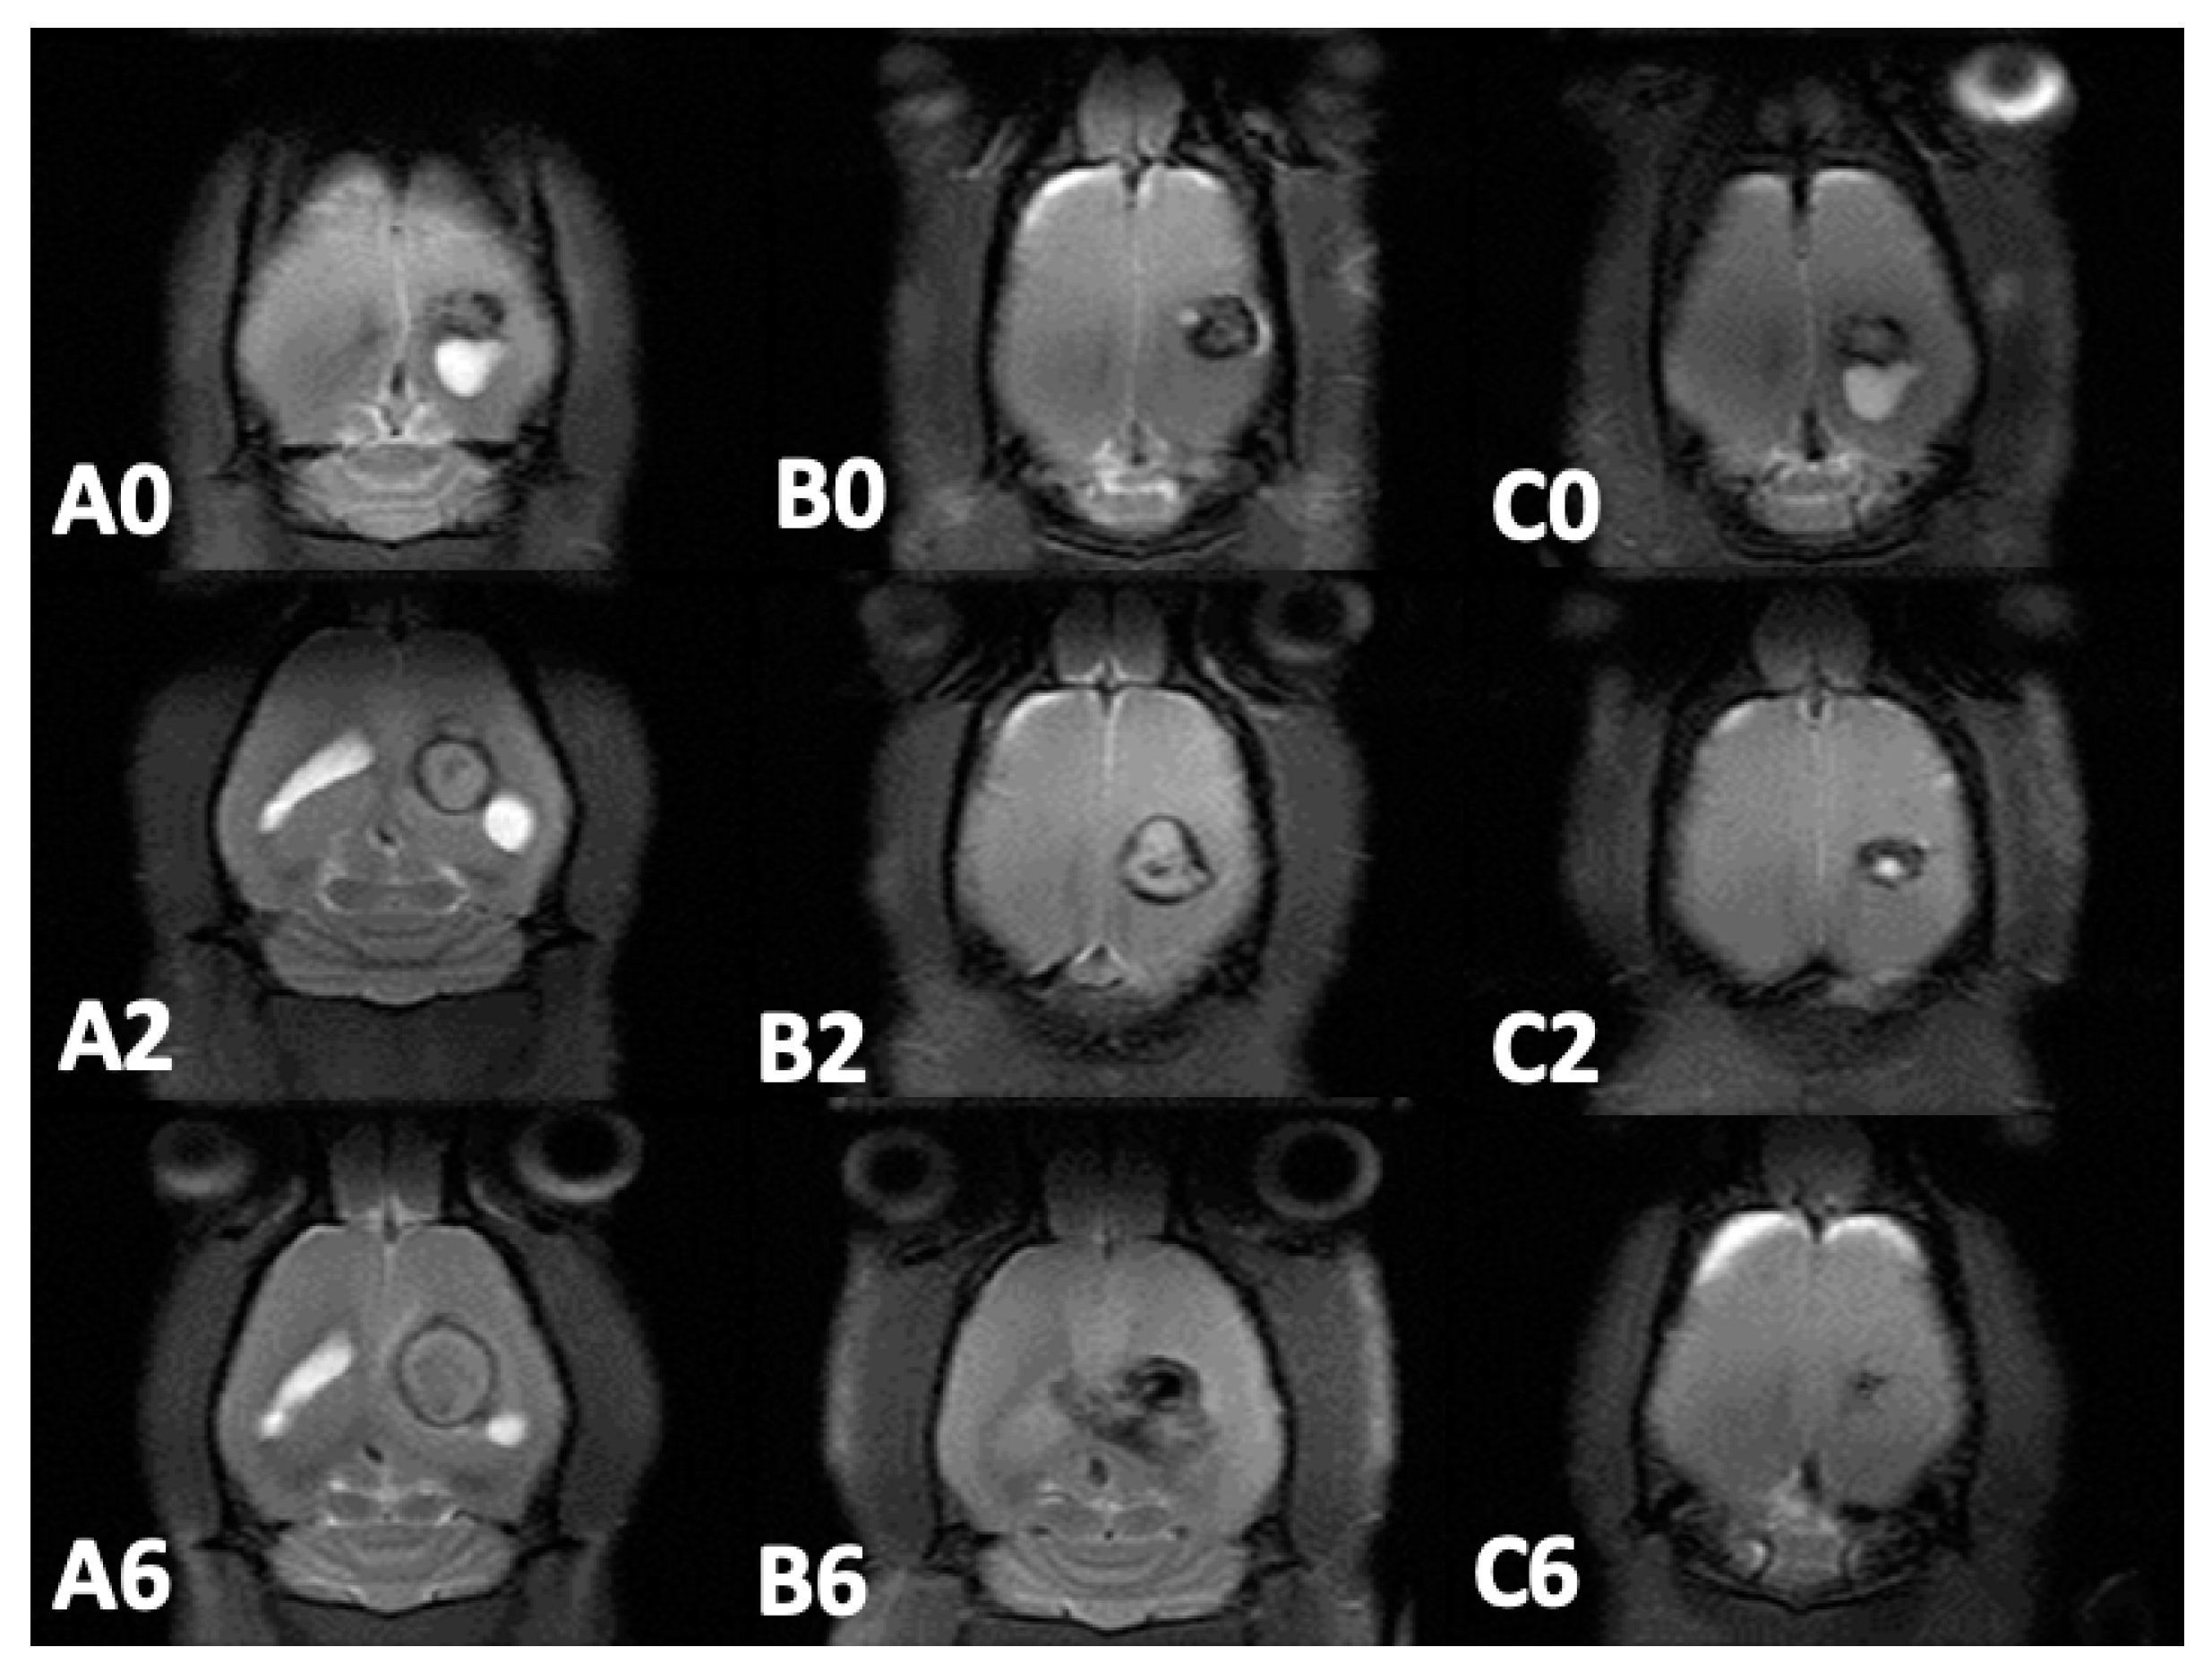

3.5. MRI and Tumor Volume